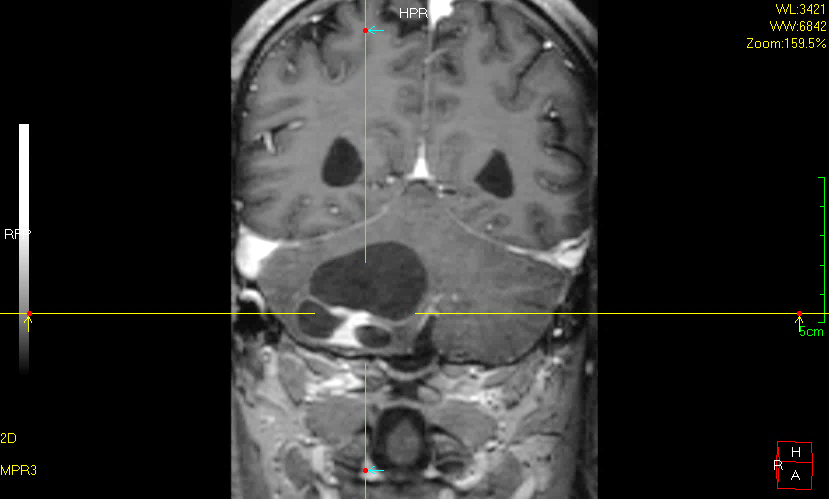

头颅MRI提示宋伯右侧小脑巨大囊实性占位,血管母细胞瘤可能性大,肿瘤实体部分不规则且靠近延髓,延髓受压变形严重,脑疝倾向,随时有生命危险。

术前头颅MRI示肿瘤巨大且呈囊实性改变